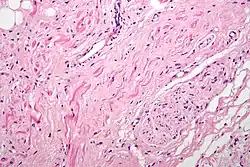

Histología

Histológicamente, el nodo sinoauricular se encuentra formado por cuatro tipos básicos de células. Las células P o pacemaker, ovoideas y pálidas, que son cardiomiocitos de despolarización.

Las células T o de transición, con una forma alargada.[7]

El otro tipo son los cardiomiocitos de trabajo, típicos de la pared auricular.

Otro tipo celular que siempre se encuentra son los fibrocitos.

Existen neuronas, las células de Purkinje, que están en íntima relación con fibras del sistema nervioso autónomo.